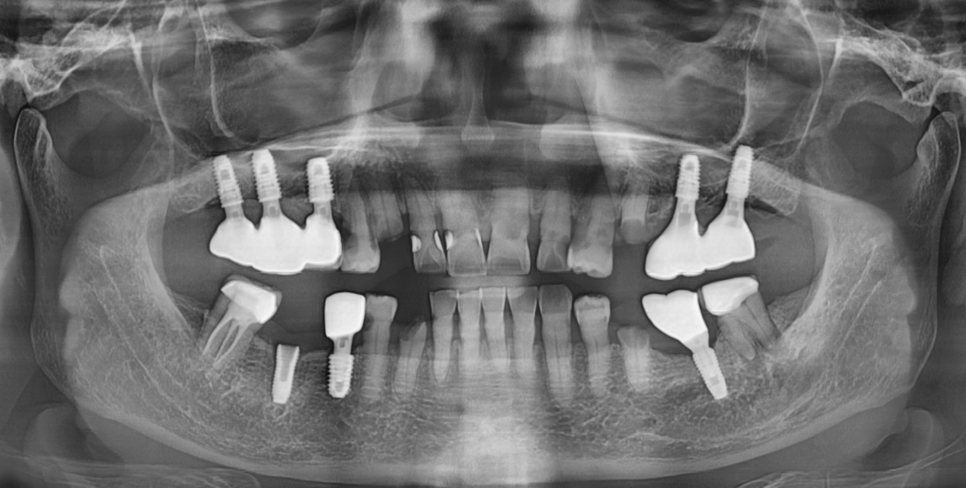

221124

대부분의 환자분들은

특히, 여러 갯수의 임플란트를 식립하신 분들의 경우

어떤 브랜드 제품인지 잘 모르시는 경우가 많습니다.

x-ray 분석 등을 통하여 최대한 제품의 정보를 확인하지만

일부 자체 개발 제품이라던가

저가형 브랜드의 경우

구조 파악에 시간이 더 걸릴 수는 있습니다.